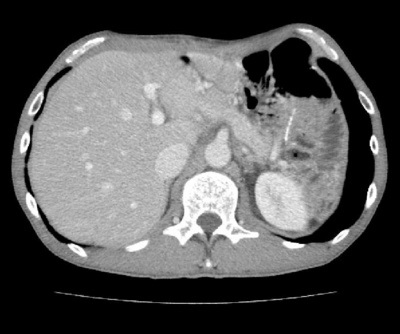

2つ目の症例の患者・Bさん(50歳代・男性)は、2012年10月に、貧血で神奈川県内の病院を受診。検査の結果、進行性の胃がん(Ⅳ期)で、肝臓に多発転移していることがわかった(写真2)。貧血が起こるまで、自覚症状はまったくなかったそうである。

写真2

Bさんは、TS–1+シスプラチンによる術前化学療法を6クール受けた。その途中、当クリニックを受診し、WT1–2+MUC1樹状細胞がんワクチンと活性化リンパ球療法を行った。その後、肝臓の画像を撮ったところ、肝転移は小さくなっていた。

胃の全摘手術後、抗がん剤と当クリニックの治療をしばらく続け、胃を全摘し、結腸部分も切除。再度、検査を受けたところ、肝臓の転移は消失していた(写真3)。

写真3